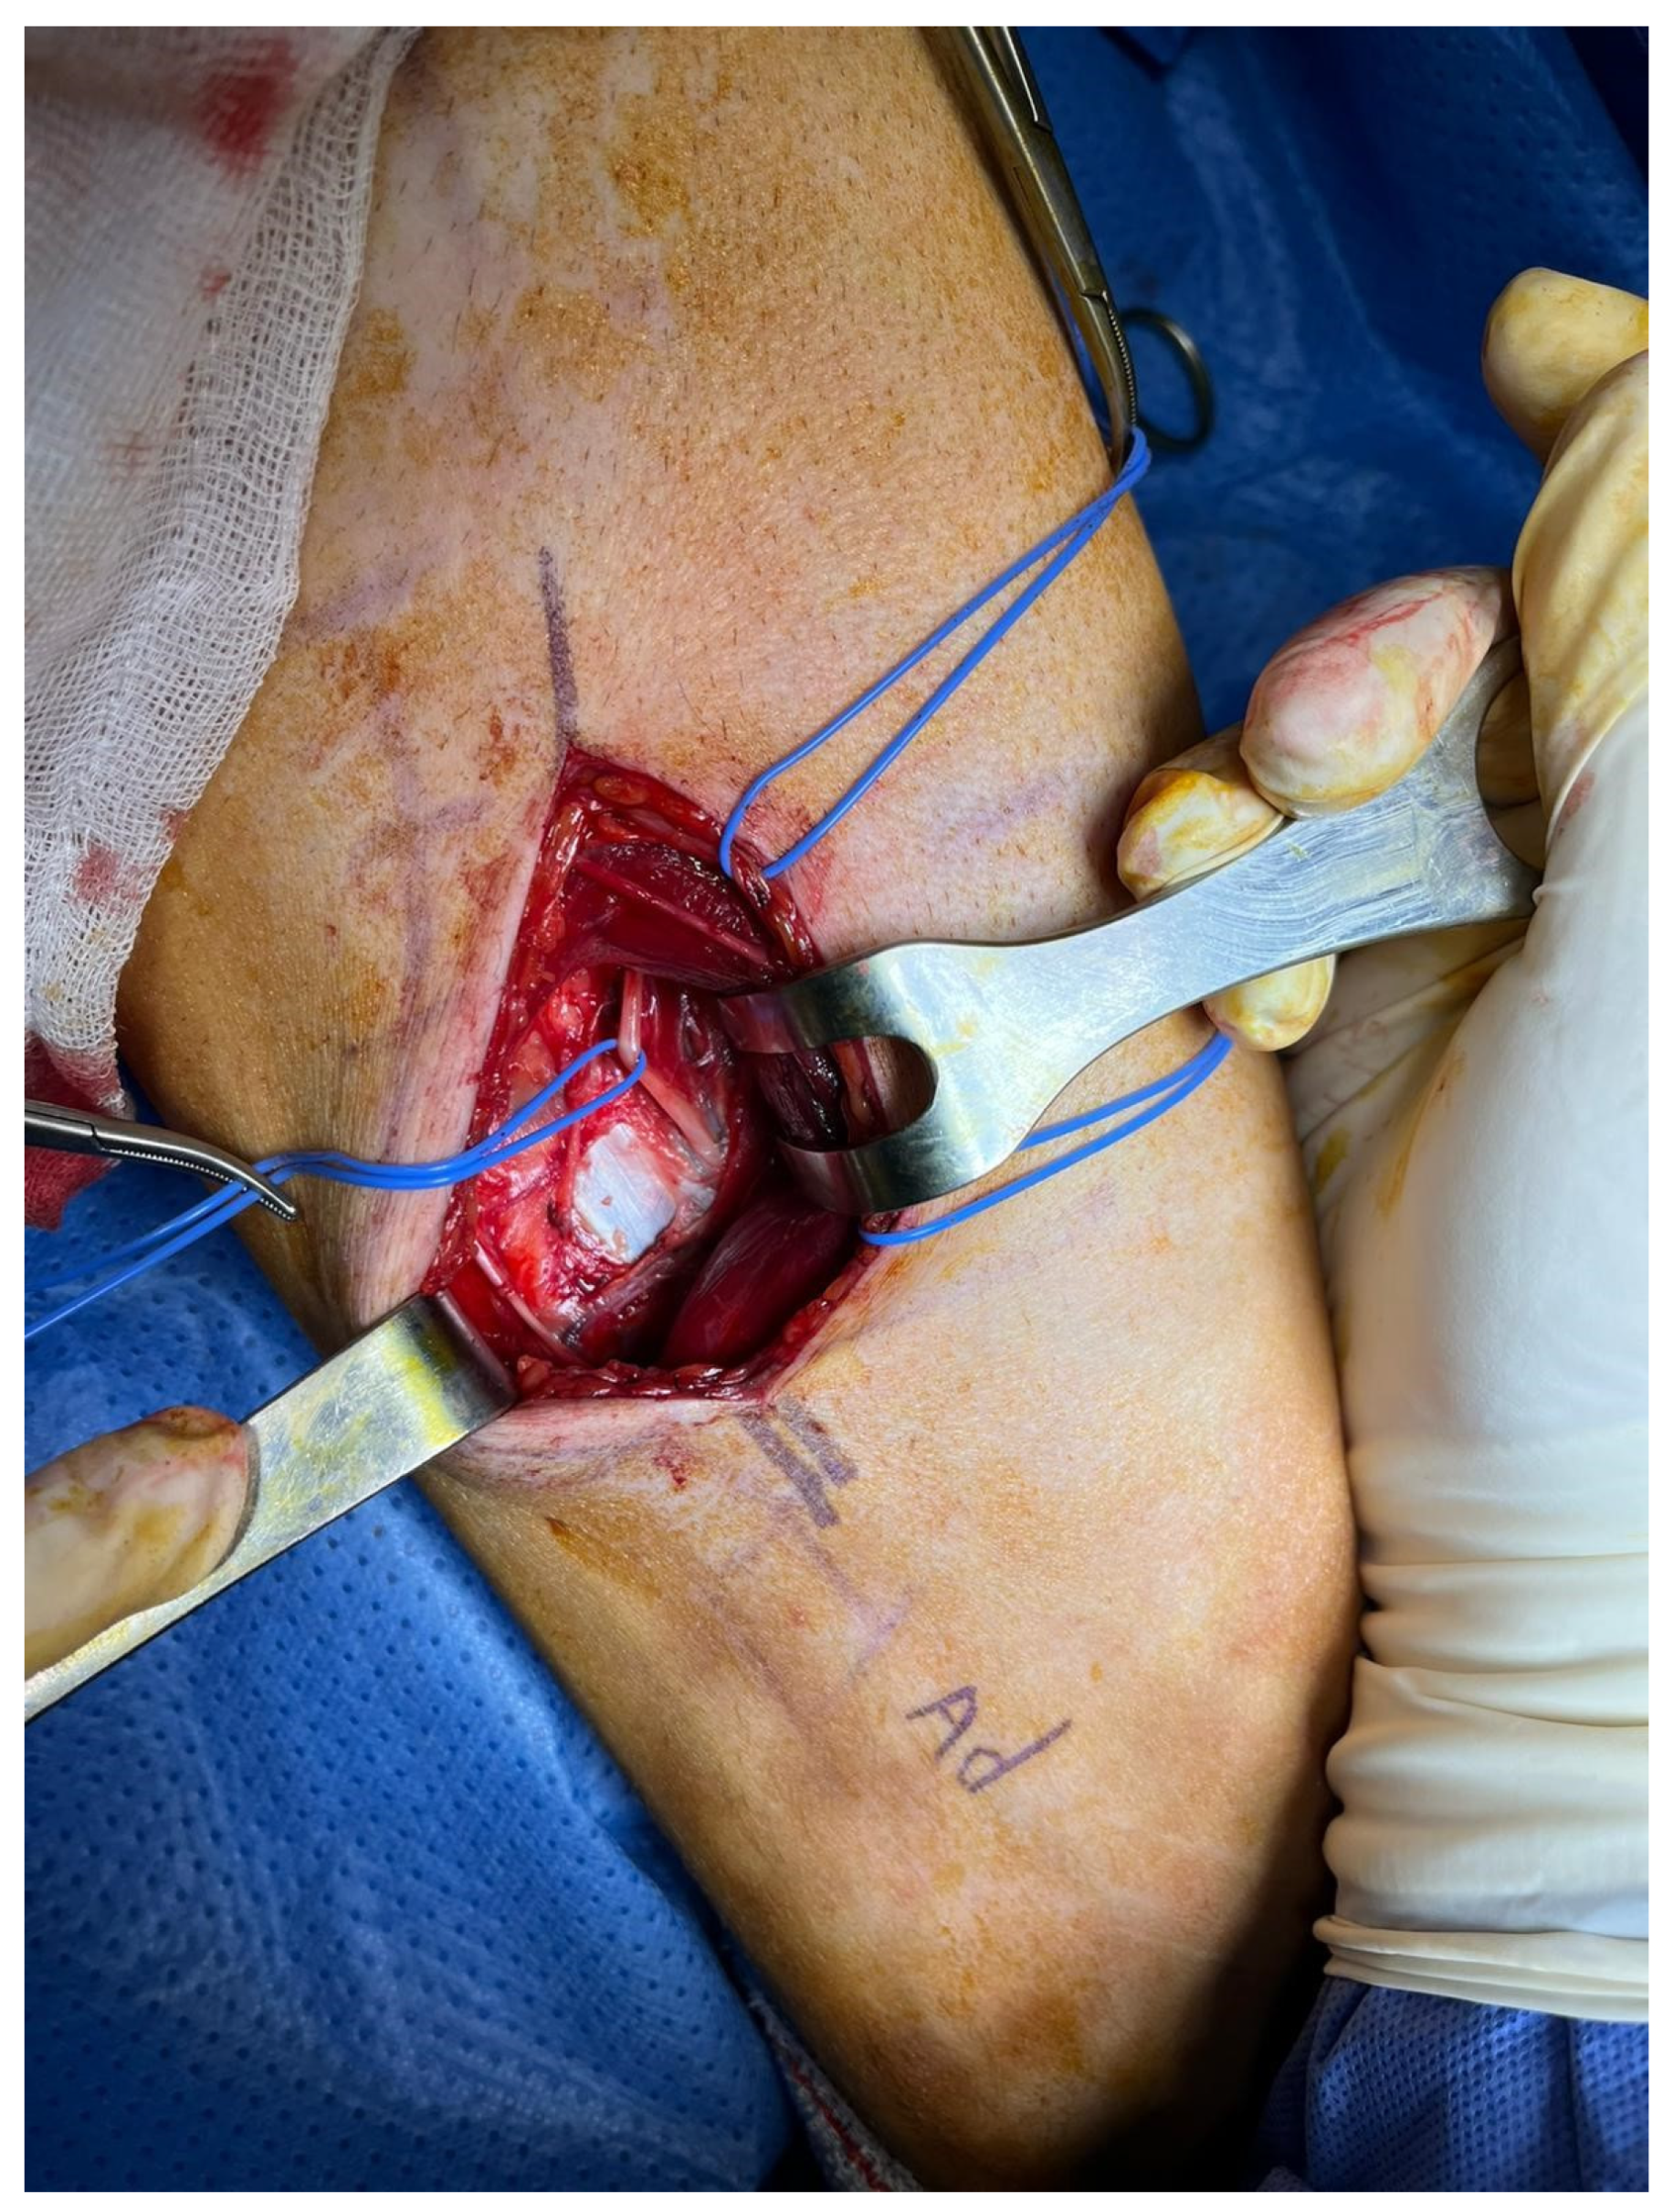

2.3. Surgical Technique